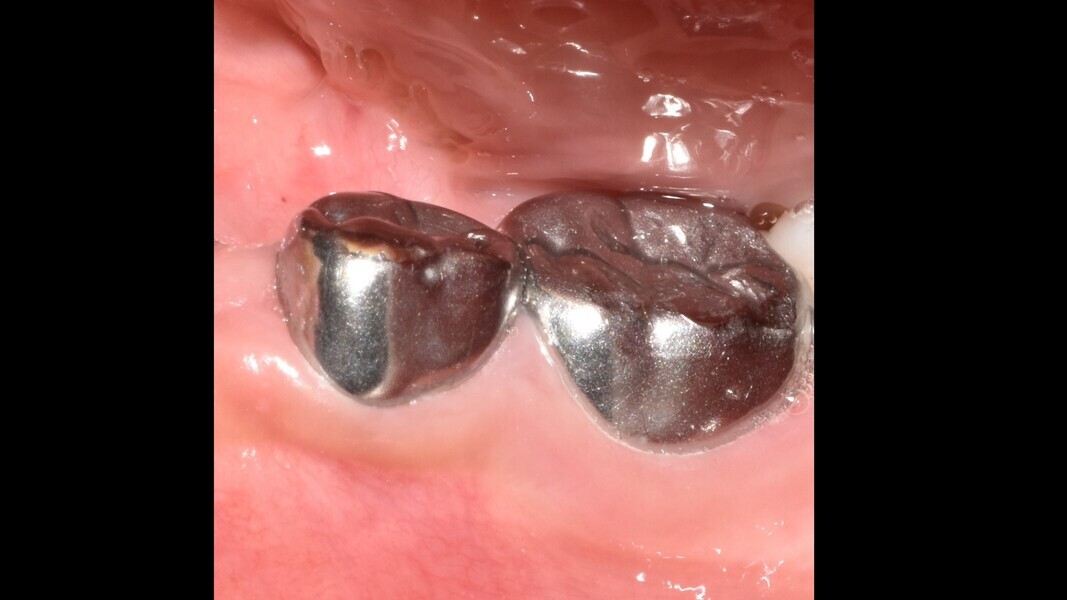

Case 2 (Figs. 5–9)

This male patient was 6 years and 7 months old and presented with severe tooth decay on the mandibular left first primary molar without any symptoms of pain. He experienced slight discomfort to percussion and palpation of the buccal gingiva. A buccal abscess and no mobility were observed. The radiograph showed a large area of interradicular bone loss. The tooth was diagnosed with pulp necrosis and an asymptomatic apical abscess. Pulpectomy was performed, and at a second appointment, a stainless-steel crown was placed upon confirming absence of signs or symptoms of disease. At the 14-month recall, no clinical pathology was detected and a normal eruptive process of the permanent premolars was observed in spite of the extrusion of the obturation material.